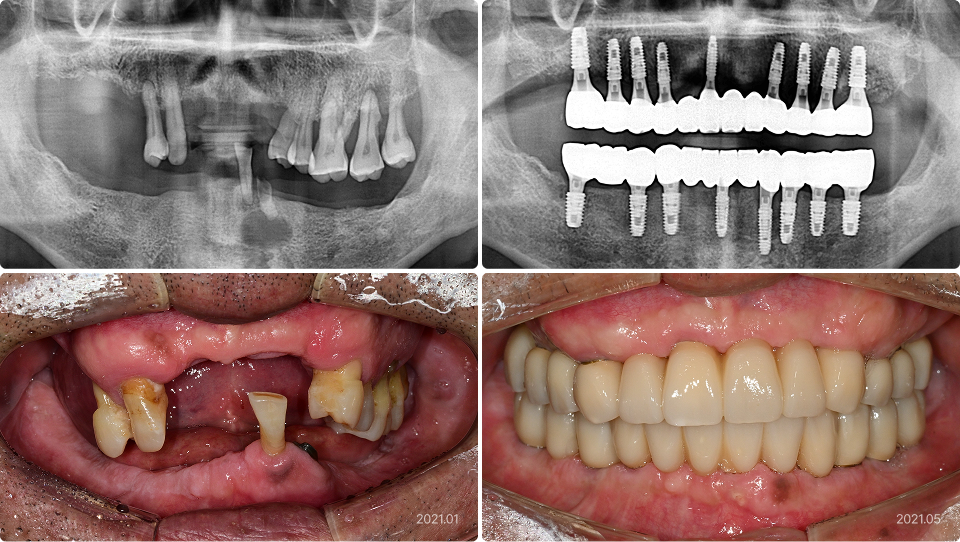

치료 전

치료 후

치료 내용

• 다수 치아 발치 및 돌출은 전체 발치 후 임플란트 식립

• 의식하진정법(수면마취)으로 상하악에 17개 임플란트 식립, 씹기 기능 회복

• 1주일에 예비치아 장착, 4개월 만에 최종치아 완성